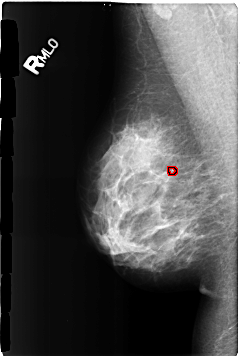

B_3169_1.RIGHT_MLO

RIGHT_MLO LINES 4624 PIXELS_PER_LINE 3112 BITS_PER_PIXEL 12 RESOLUTION 50 OVERLAY

FILE: B_3169_1.RIGHT_MLO.OVERLAY

TOTAL_ABNORMALITIES 1

ABNORMALITY 1

LESION_TYPE CALCIFICATION TYPE LUCENT_CENTER DISTRIBUTION N/A

ASSESSMENT 2

SUBTLETY 3

PATHOLOGY BENIGN_WITHOUT_CALLBACK